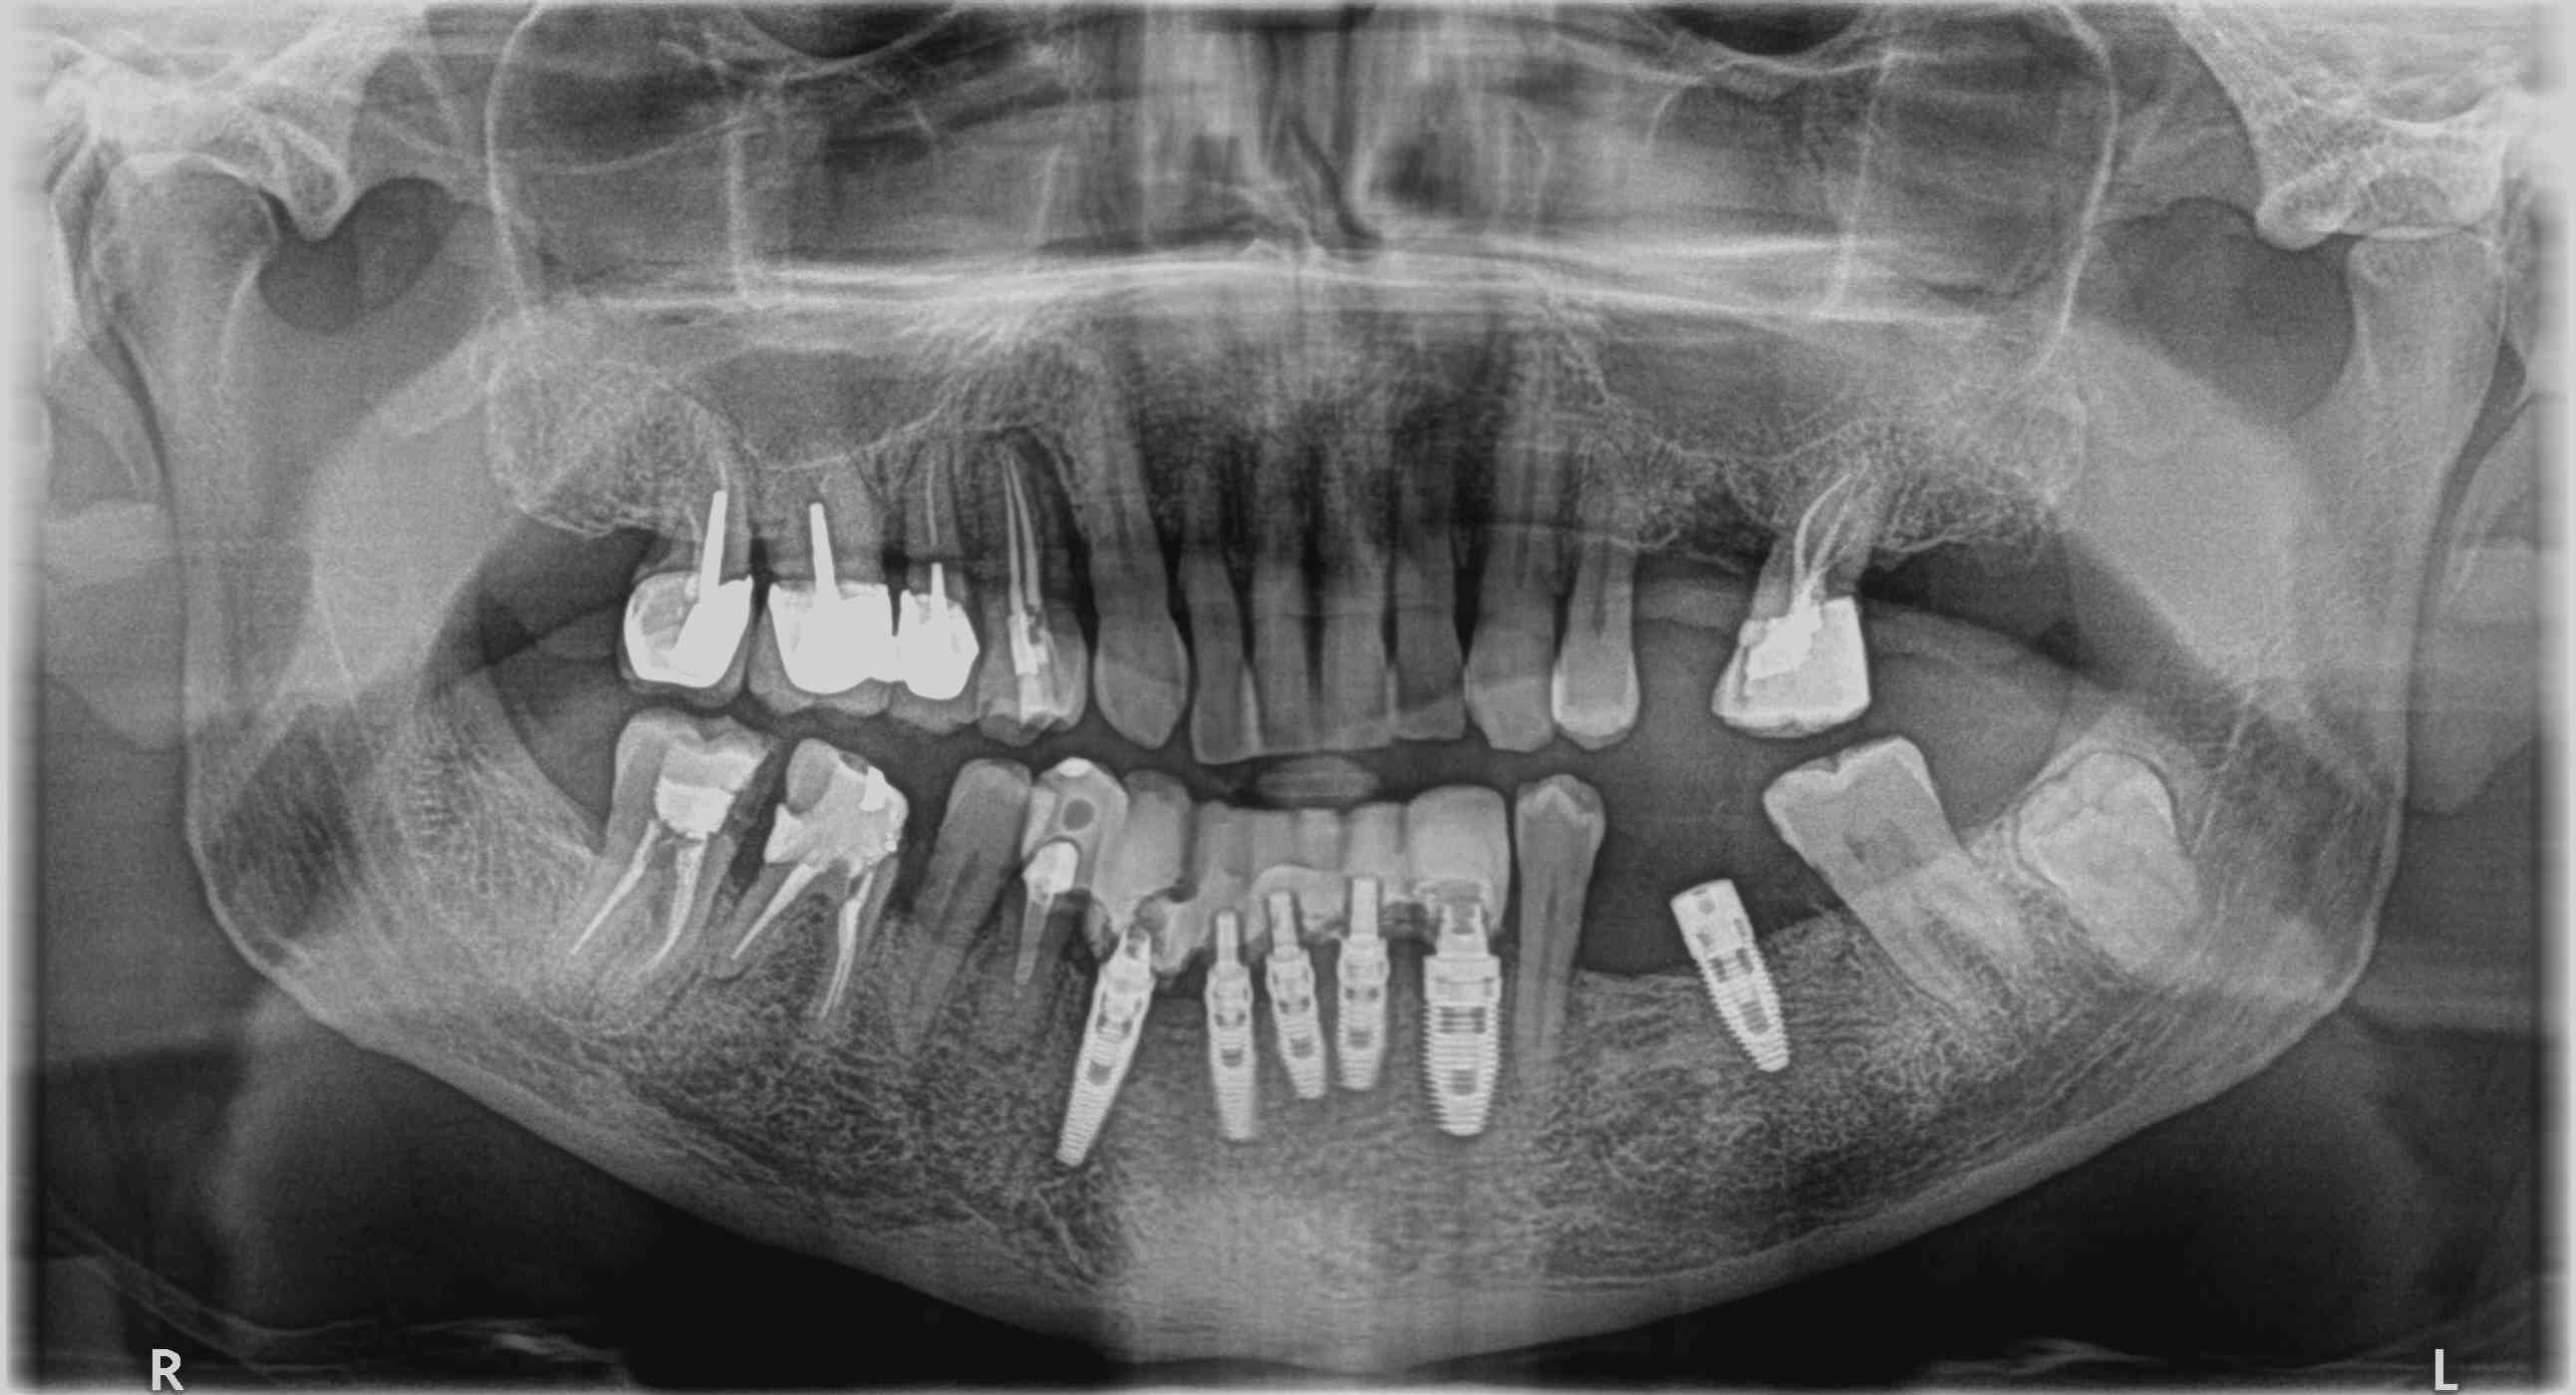

j'ai hérité d' un patient qui s'est fait mettre 6 implants en urgence ... dans un pays lointain.... (maurice)

j'ai pas trouvé sur whatimplant is that ... (je bute sur ces spires très rapprochées)

j'ai pu dévisser sur la 36 avec un tournevis camlog , mais d'après la connexion c'est pas du camlog.

connexion trilobe violette, marquage 5mm sur la vis cicat.

ensuite sur les implants en canines ça pourrait être du multi unit?

et sur les incisives ???

sur les canines c'est des multiunit

sur les incisives c'est des post provisoires (une tige hexagonales vissée sur laquelle vient se mettre un pilier plastique provisoire)

finalement c'est du "southern implant tri nex " ....

je me disais bien que le nombre de spires ne correspondait pas à du nobel...